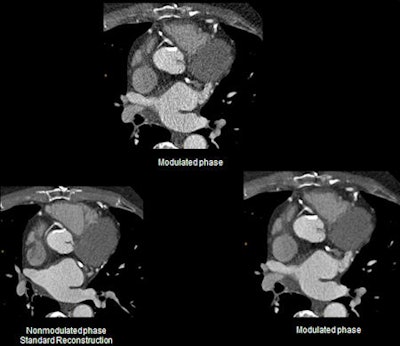

Sophisticated image reconstruction algorithms have been developed over the past few years. A key factor has been the significant increase in computing power necessary for image reconstruction algorithms beyond standard filtered back projection (FBP). At the TUM, radiologists have worked on the clinical integration of iDose from Philips Healthcare on a 256-slice multidetector CT unit (Brilliance iCT) to lower radiation dose while retaining an image quality at least equal to standard FBP reconstruction. They presented their findings at the recent RSNA congress.

Before the integration of iDose in clinical routine, Fingerle and his colleagues evaluated the algorithm's performance in a preclinical phantom study. They assessed CT number uniformity, low contrast quality, noise characteristics, and spatial resolution. When applying the iDose algorithm to low-dose CT protocol (120kV, 50 mAs), CT numbers were revealed in the level of standard dose FBP reconstructions (120kV, 250 mAs). Calculations of the modulation transfer function with a wire phantom and visual evaluation of the bar pattern of a Catphan 600 phantom showed no decrease in resolution with the use of iDose.